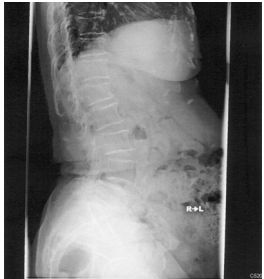

39 70 歲呂老太太腰酸痛已經八年,症狀反覆發作時好時壞,勞作後症狀加劇。經檢查發現 X 光如圖所 示,則其診斷應為何?

(A)椎間盤脫出 (B)脊椎滑脫 (C)椎管狹窄症 (D)僵直性脊椎炎